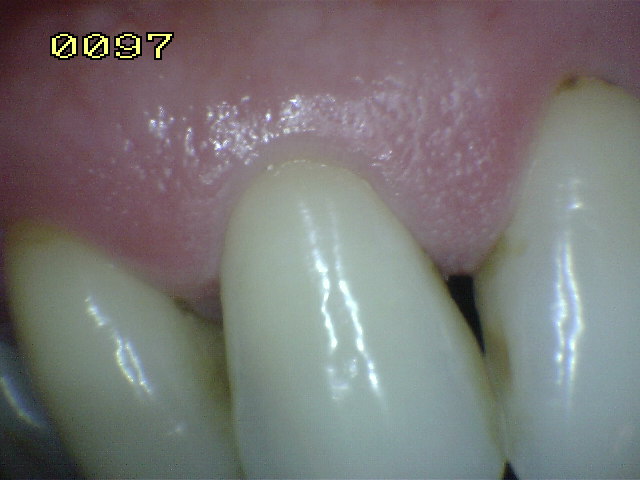

Encía Normal |